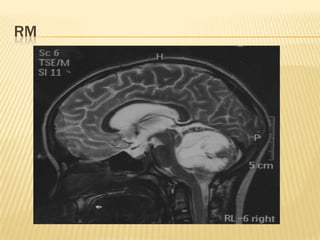

   La imagen de resonancia magnética permite la localización anatómica de la

lesión, las características tisulares del tumor y la vascularidad. Este método

con gadolinio es también sensible para evaluar la metástasis subaracnoidea

de la médula espinal. Debido a que en algunas ocasiones el meduloblastoma se